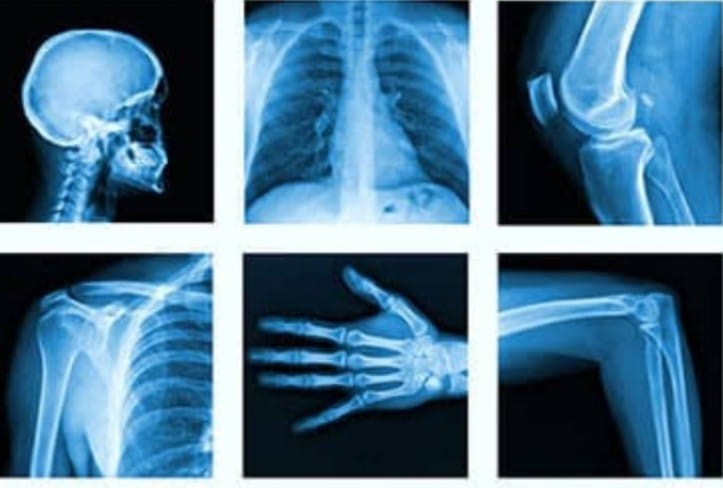

Through Meena’s eyes, we see the value of such X-Ray services. They provide not just a practical solution— a clear image to diagnose her condition— but also emotional relief. The service bridges the gap between fear and knowledge, offering clarity and peace of mind.

In Meena’s case, the X-Ray revealed a minor issue that could be managed with physiotherapy and lifestyle changes. With this new knowledge, the burden of fear lifted, and she felt empowered to take control of her health. The diagnostic center didn’t just offer a service; they offered hope and a path forward.

This transformation in Meena’s life is a testament to the impact that accessible and reliable healthcare services can have. For many like her, an X-Ray service is not just a medical tool, but a beacon of hope that illuminates the path towards healing and well-being.

The story of Meena is not just about overcoming pain; it’s about reclaiming life. Her journey from fear to empowerment highlights the essential role that X-Ray services play in our lives. They unravel the mysteries of our bodies, providing answers and peace of mind.